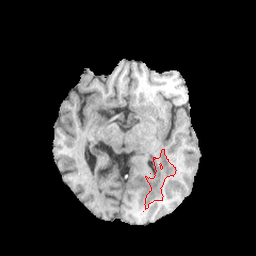

Refer to caption

(a)

(b)

(c)

(d)

(e)

(f)

(g)

(h)

Figure 2: Samples patches from BCSS (a-d) and BraTS 2020 (e-h) with their respective tumor ground truths marked in red.

As the focus of this work is on possible applications of SAM in the medical domains, we evaluate on the radiology dataset BraTS and the pathology dataset BCSS. Figure 2 shows sample patches from both datasets. The following sections provide more details on each dataset.